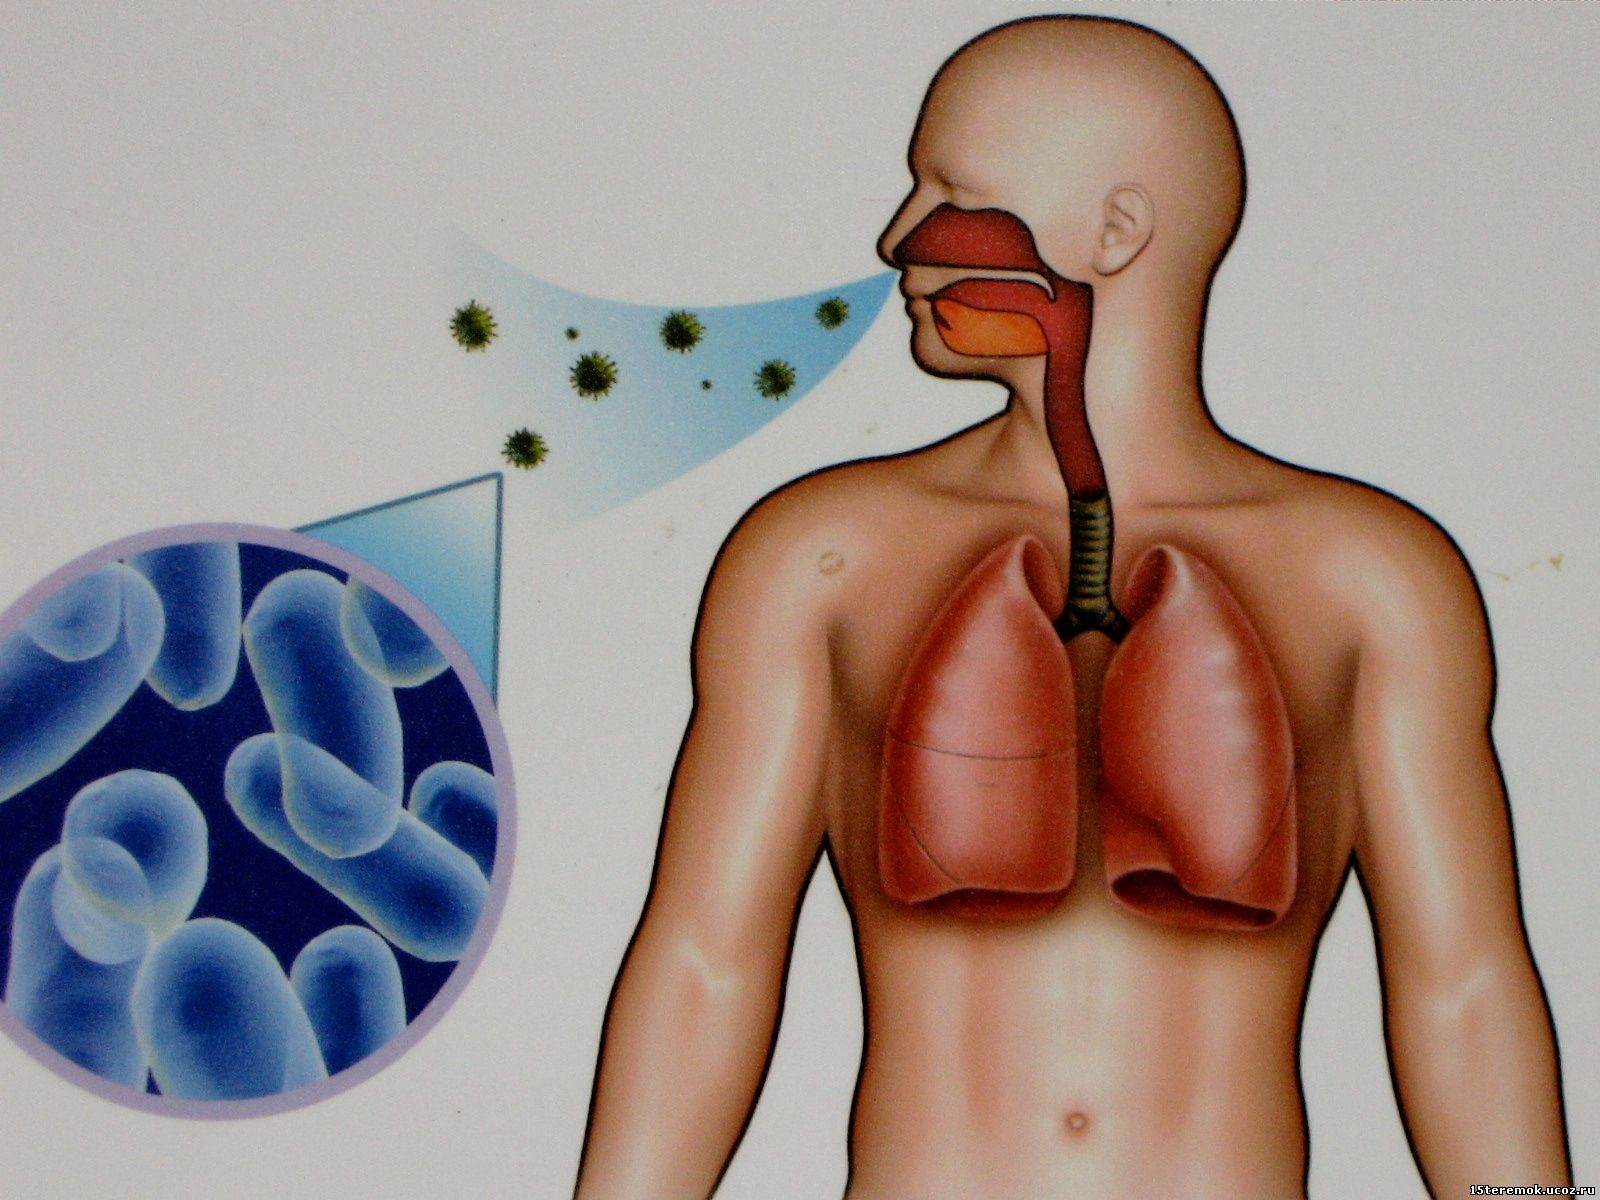

Фотографии бактерий, вызывающих бактериальные пневмонии у животных

Раздел: Другие животные